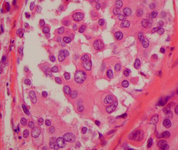

Histopathology of pleomorphic lobular carcinoma in situ (LCIS)

Courtesy of Dr Sunati Sahoo, University of Louisville; used with permission